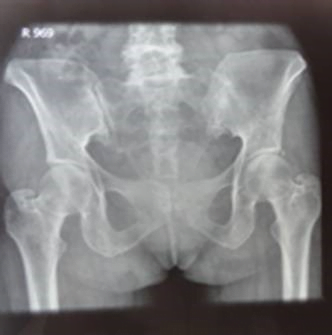

Examination of the spine showed kyphoscoliosis with normal spinal mobility. X-ray of pelvis showed normal sacroiliac joint (Fig. 1).

Fig. 1: X-ray showing pelvis with normal sacroiliac joint

Ankylosing spondylitis is associated with sacroiliitis, and the patient's X-ray showed a pelvis with a normal sacroiliac joint, making it less likely to be the cause. The symptoms, family history, and clinical presentation are more suggestive of conditions other than ankylosing spondylitis.